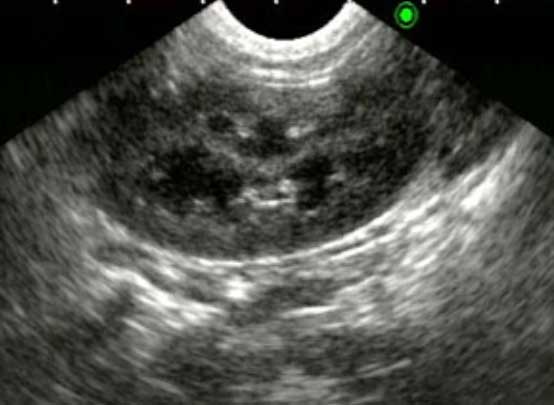

超音波検査

腎臓や膀胱の内部構造を確認します。腎臓においては形態や構造の変化、血流の評価を、膀胱においては壁の厚さや不整、内部の結石や血餅などの評価を行います。その他にも、尿管や尿道、雌では子宮や卵巣、雄は前立腺の評価にも有用です。

膀胱腫瘍

犬の悪性腫瘍の2%を占める腫瘍です。症状が血尿、頻尿、排尿困難など下部尿路疾患と似た症状であり、抗生剤の投与により一時的に症状が改善されることから、発見が遅れる可能性があります。しかし、尿道や尿管開口 部での発生が多く、転移しやすい、より悪性度の高い腫瘍であることが多いのが実情です。早期発見・早期治療 のため、泌尿器症状が長引く場合には超音波検査などの画像検査による精査をおすすめします。

膀胱腫瘍(移行上皮癌)